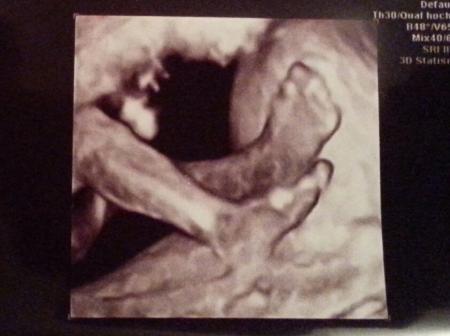

oh man das ist ja auch so gar nicht nett mit deiner Schwiegermutter. naja so ähnlich läuft es bei uns ja im Grunde auch. ich finde es so schlimm das sich Großeltern so extrem auf ein Geschlecht fixieren. es ist doch nicht denen ihr Leben. die hatten doch viele Jahre Zeit zum Kinder kriegen und sich Geschlechter wünschen. unser eins ist einfach nur dankbar ein hoffentlich gesundes Baby im Bauch zu haben und die sind so vermessen. ich meine ihr hattet einen langen und sicher steinigen Weg, ich habe genug durch den Job gesehen und erzähle da ja auch gelegentlich von - unsere Familien sollten doch eigentlich wissen das das Geschlecht ganz schön unwichtig ist! Auch wenn sie diese Sprüche vielleicht nicht so meinen, es ist verletzend und irgendwie respektlos finde ich :-( ja die Bilder sind wirklich toll und faszinierend. in meiner ersten Schwangerschaft war ich mal notfallmäßig bei einer vertretungsärztin. die hat dann plötzlich auf 3d umgestellt. da war ich so naff. hatte nie viel auf solche Bilder gegeben. jedenfalls bekam ich diese Fotos nicht ausgedruckt, ich war so enttäuscht und frustriert das diese wildfremde Person die "ersten Fotos" MEINES Kindes besitzt und das ich die nicht mal meinem Mann zeigen konnte. jedenfalls hab ich mich echt gequält und dann beschlossen für 60 € einen ganz offiziellen 3d Schall machen zu lassen. habe alle Bilder und Videos auf einen Stick bekommen. das war dann bei 37+0. da sieht man meistens ja nicht mehr so viel weil die kleinen kaum noch Platz haben und zu tief im Becken liegen. aber ich hatte ohnehin recht viel fruchtwasser und Felix ist erst unter der Geburt ins Becken gerutscht, so hatten wir eine tolle Sicht. die ganzen Arzthelferinnen wurden nach und nach zum gucken rein geholt weil die Ärztin sagte so spät sieht man selten er Kind so gut. hänge mal was dran

Ja da hast du recht finde es auch respektlos und bin auch wütend mein freund meint dann immer ich soll das nicht ernst nehmen leichter gesagt als getan... Ja der weg war echt nicht einfach aber ich hab nicht aufgegen und jetzt darf ich dieses wunder endlich erleben und genießen freue mich schon extrem auf die zeit ;-) Wollte auch bei diesen ultraschall einen 3d haben aber meine ärztin meinte es ist besser beim nächsten termin das zu machen aber wo ich jetzt deine maus gesehen habe .... Aber naja muss ich mich noch gedulden. Hoffe das es auch so schöne bilder werden. Wahnsinn wow die fotos von felix sind ja der wahnsinn!!!!!! Also so eine gute qualität hab ich ja noch nie gesehen.... Hab mir auf google einige angeschaut und deine bilder sind ja gestochen scharf ... Die haben ja ein sehr gutes gerät gehabt. Echt ein wunder!!!! Schöne babys habt ihr gemacht :-) Die fotos muss ich heut gleich mal meinen freund zeigm bin grad so begeistert von dieser qualität. Du bist ja hebamme oder ? :-)